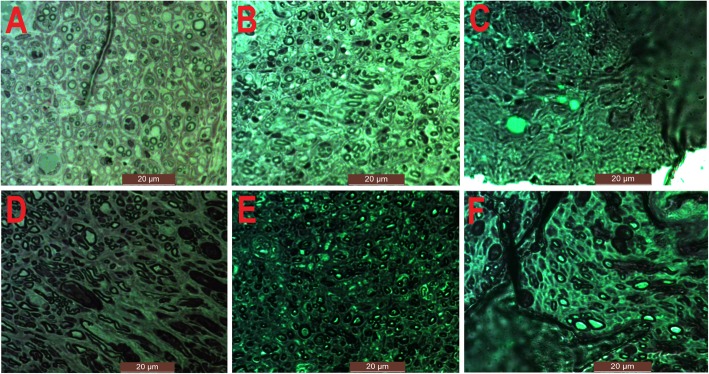

Nerve fiber count

Median and axillary nerves were biopsied from the affected side in Group A and B, respectively. Both of the two nerves were obtained in Group C and D. All nerve sections were taken near their entry points into the target muscles. The samples were fixed in 25% glutaraldehyde (Shanghai Reagent Company, Shanghai, China) and embedded with paraffin for slices. Then they were stained with 5% toluidine blue (Shanghai Reagent Company, Shanghai, China). The average number of nerve fibers in unit area was measured and calculated by the Image J system.

Nerve fiber count

Figure 5b showed the differences in the number of nerve fibers in different groups. The numbers of median nerve fibers were 17.67 ± 3.06/mm2 in Group A and 13.33 ± 3.06/mm2 in Group C. There was no significant difference in the number of median nerve fibers between the two groups. However, either the number of median nerve fibers in Group A or C was significantly more than that in Group D (7.00 ± 2.00/mm2). The numbers of axillary nerve fibers were 13.00 ± 2.00/mm2, 11.33 ± 3.21/mm2 and 6.33 ± 1.53/mm2 in Group B, C and D, respectively. Either the number of axillary nerve fibers in Group B or C was significantly more than that in Group D. There was no statistical difference in the number of axillary nerve fibers between Group B and C. In Group C, the number of median nerve fibers (13.33 ± 3.06/mm2) was more than that of axillary nerve fibers (11.33 ± 3.21/mm2) without a significant difference. The number of median nerve fibers in Group A (17.67 ± 3.06/mm2) was more than that of axillary nerve fibers in Group B (13.00 ± 2.00/mm2) without a significant difference. Figure 6 showed different nerve fibers in different groups.

Fig. 6.

a The nerve fibers of median nerve in Group A. b The nerve fibers of median nerve in Group C. c The nerve fibers of median nerve in Group D. d The nerve fibers of axillary nerve in Group B. e The nerve fibers of axillary nerve in Group C. f The nerve fibers of axillary nerve in Group D